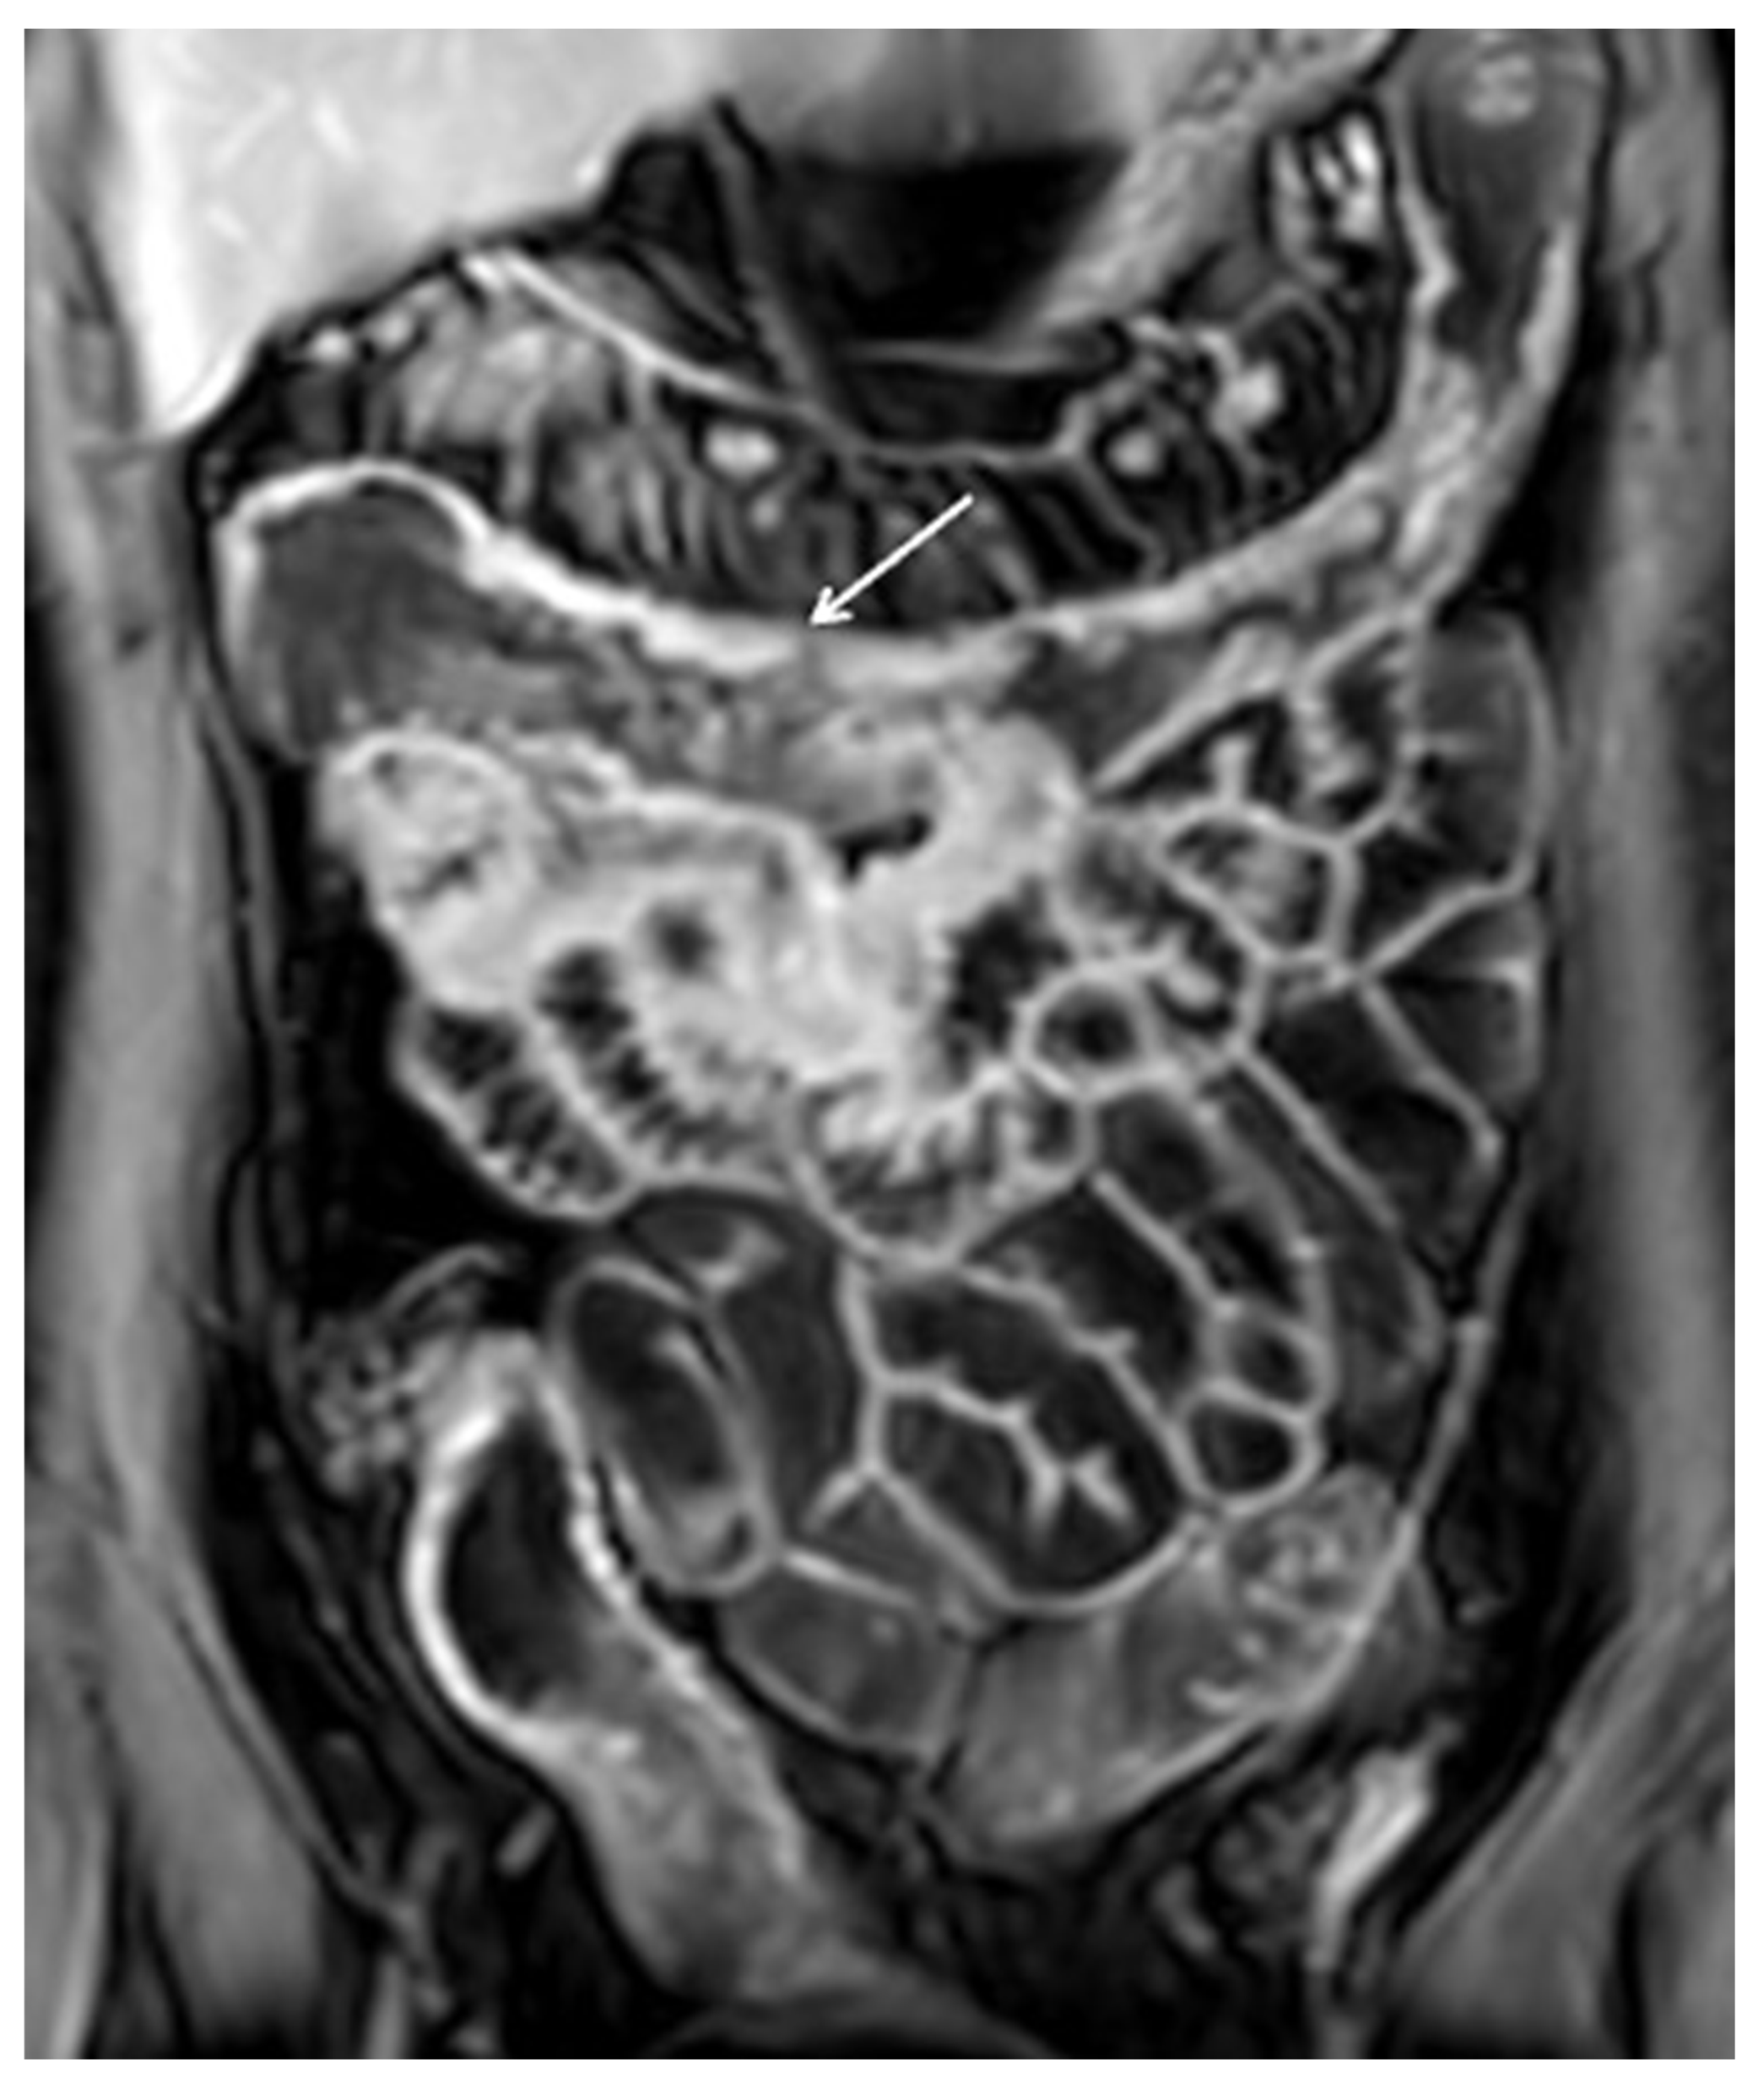

12. Imaging Findings Associated with Non-Active CD Inflammation

- Fornasa, F.; Benassuti, C.; Benazzato, L. Role of mag-netic resonance enterography in differentiating be-tween fibrotic and active inflammatory small bowel stenosis in patients with Crohn’s disease. J. Clin. Imaging Sci. 2011, 1, 35. [Google Scholar] [CrossRef]

- Burke, J.P.; Mulsow, J.J.; O’Keane, C.; Docherty, N.G.; Watson, R.W.G.; O’Connell, P.R. Fibrogenesis in Crohn’s Disease. Am. J. Gastroenterol. 2007, 102, 439–448. [Google Scholar] [CrossRef] [PubMed]

- Steward, M.J.; Punwani, S.; Proctor, I.; Adjei-Gyamfi, Y.; Chatterjee, F.; Bloom, S.; Novelli, M.; Halligan, S.; Rodriguez-Justo, M.; Taylor, S. Non-perforating small bowel Crohn’s disease assessed by MRI enterography: Derivation and histopathological validation of an MR-based activity index. Eur. J. Radiol. 2012, 81, 2080–2088. [Google Scholar] [CrossRef]

- Rimola, J.; Ordás, I.; Rodriguez, S. Magnetic resonance imaging for evaluation of Crohn’s disease: Validation of parameters of severity and quantitative index of activity. Inflamm. Bowel Dis. 2011, 17, 1759–1768. [Google Scholar] [CrossRef]

- Rimola, J.; Planell, N.; Rodríguez, S.; Delgado, S.; Ordás, I.; Ramírez-Morros, A.; Ayuso, C.; Aceituno, M.; Ricart, E.; Jauregui-Amezaga, A.; et al. Characterization of Inflammation and Fibrosis in Crohn’s Disease Lesions by Magnetic Resonance Imaging. Am. J. Gastroenterol. 2015, 110, 432–440. [Google Scholar] [CrossRef]

- Latella, G.; Sferra, R.; Speca, S.; Vetuschi, A.; Gaudio, E. Can we prevent, reduce or reverse intestinal fibrosis in IBD? Eur. Rev. Med. Pharmacol. Sci. 2013, 17, 1283–1304. [Google Scholar]

- Foti, P.; Travali, M.; Farina, R.; Palmucci, S.; Coronella, M.; Spatola, C.; Puzzo, L.; Garro, R.; Inserra, G.; Riguccio, G.; et al. Can Conventional and Diffusion-Weighted MR Enterography Biomarkers Differentiate Inflammatory from Fibrotic Strictures in Crohn’s Disease? Medicina 2021, 57, 265. [Google Scholar] [CrossRef] [PubMed]

- Tielbeek, J.A.W.; Ziech, M.L.W.; Li, Z.; Lavini, C.; Bipat, S.; Bemelman, W.A.; Roelofs, J.J.T.H.; Ponsioen, C.Y.; Vos, F.M.; Stoker, J. Evaluation of conventional, dynamic contrast enhanced and diffusion weighted MRI for quantitative Crohn’s disease assessment with histopathology of surgical specimens. Eur. Radiol. 2013, 24, 619–629. [Google Scholar] [CrossRef]

- Barkmeier, D.T.; Dillman, J.R.; Al-Hawary, M.; Heider, A.; Davenport, M.S.; Smith, E.A.; Adler, J. MR enterography–histology comparison in resected pediatric small bowel Crohn disease strictures: Can imaging predict fibrosis? Pediatr. Radiol. 2015, 46, 498–507. [Google Scholar] [CrossRef] [PubMed]

- Caruso, A.; Angriman, I.; Scarpa, M.; D’Incà, R.; Mescoli, C.; Rudatis, M.; Sturniolo, G.C.; Schifano, G.; Lacognata, C. Diffusion-weighted magnetic resonance for assessing fibrosis in Crohn’s disease. Abdom. Radiol. 2019, 45, 2327–2335. [Google Scholar] [CrossRef] [PubMed]